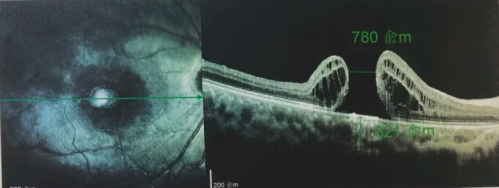

由于自身患有頸椎病,每次術后長期的趴睡都讓他痛苦不堪。為了尋求更好的治療,吳爺爺來到廈門大學附屬廈門眼科中心,找到了眼外傷及眼底病2科的李海波博士后。此時,吳爺爺右眼的黃斑裂孔已經持續(xù)擴大到780μm,演變?yōu)殡y治性的大裂孔。

最讓吳爺爺難以置信的是:術后只需保持平躺24小時!第二天復查時,眼底鏡及OCT檢查清晰顯示——那個折磨了他大半年的大裂孔,竟然閉合了!且吳爺爺的右眼視力有了明顯的改善,術后3天已經可以看到 0.15。